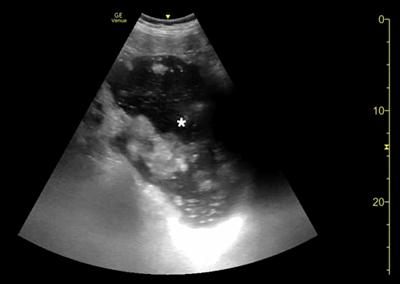

腹部床旁超声检查(POCUS)显示,胃部扩张并充满液体,高度疑似梗阻(图1,2)。

(图2)

当怀疑有胃扭转时,选择初始的影像学检查非常重要,因为诊断延迟可能导致致命的并发症。CT检查高度可靠,主要有两种表现,即正常的胃窦幽门移行区和胃窦位置异常,诊断急性胃扭转的敏感性和特异性均为100%。POCUS是一种有效的非侵入性影像检查方式,主要用于床旁评估。此外,POCUS无辐射,并可根据临床情况随时进行重复检查。本例患者POCUS检查显示,胃部严重扩张,胃内容物分层,类似胃出口梗阻(GOO)的“黑白饼干”征象。POCUS还可以用来动态观察胃减压成功与否。